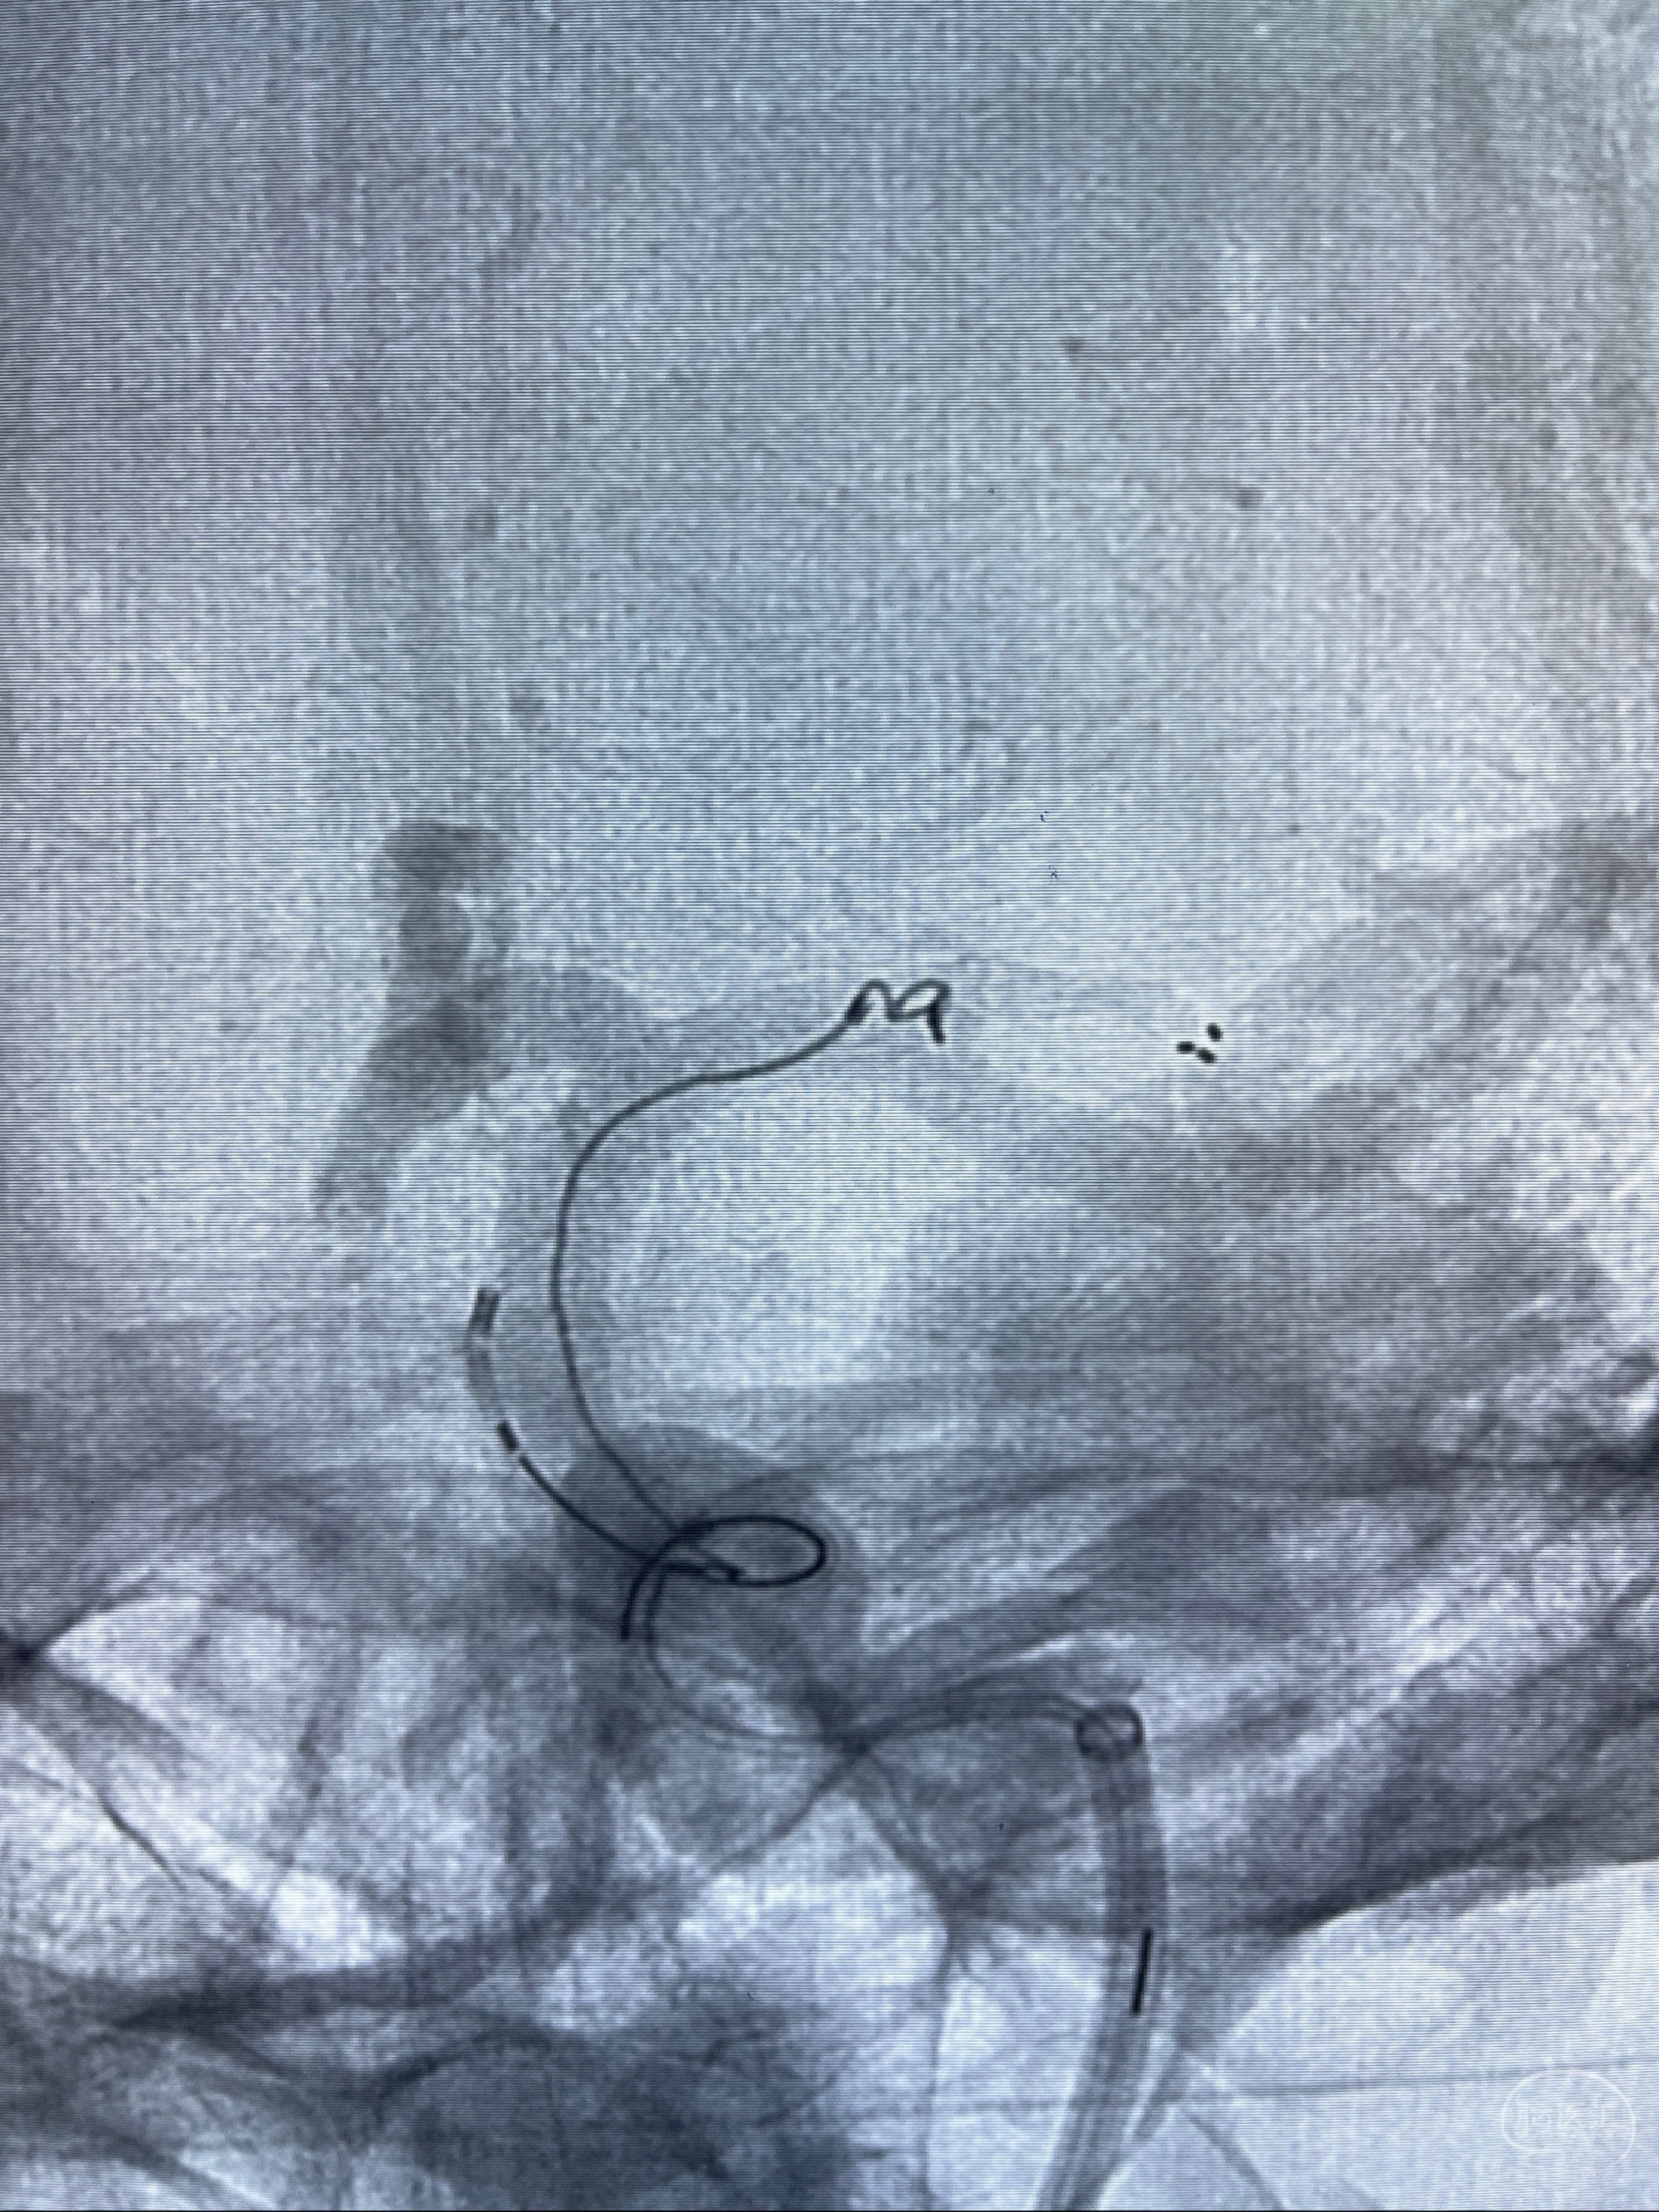

2023-08-14DSA:

左侧大脑中动脉动脉瘤,约2.6-2.8-3.4-2mm大小(瘤颈部、瘤体部、瘤高)